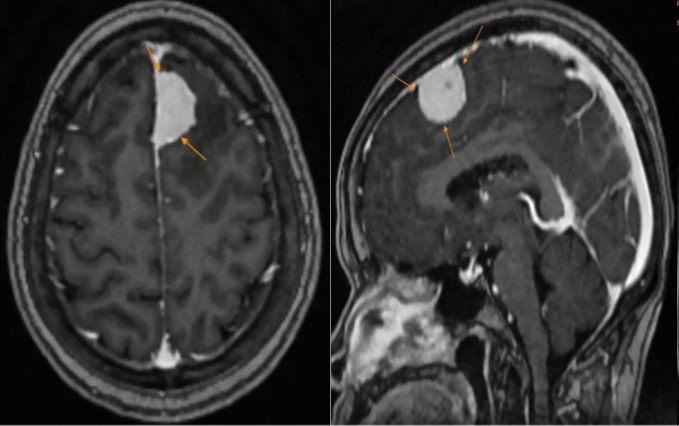

Phim chụp của bệnh nhân.

Kết quả MRI khiến cô H. bất ngờ khi có một khối u lớn vùng trán trái, kích thước khoảng 27x15mm, nghi ngờ u màng não. Nhờ phát hiện kịp thời, bác sỹ đã tư vấn phương án can thiệp an toàn và hiệu quả, hạn chế rủi ro biến chứng.